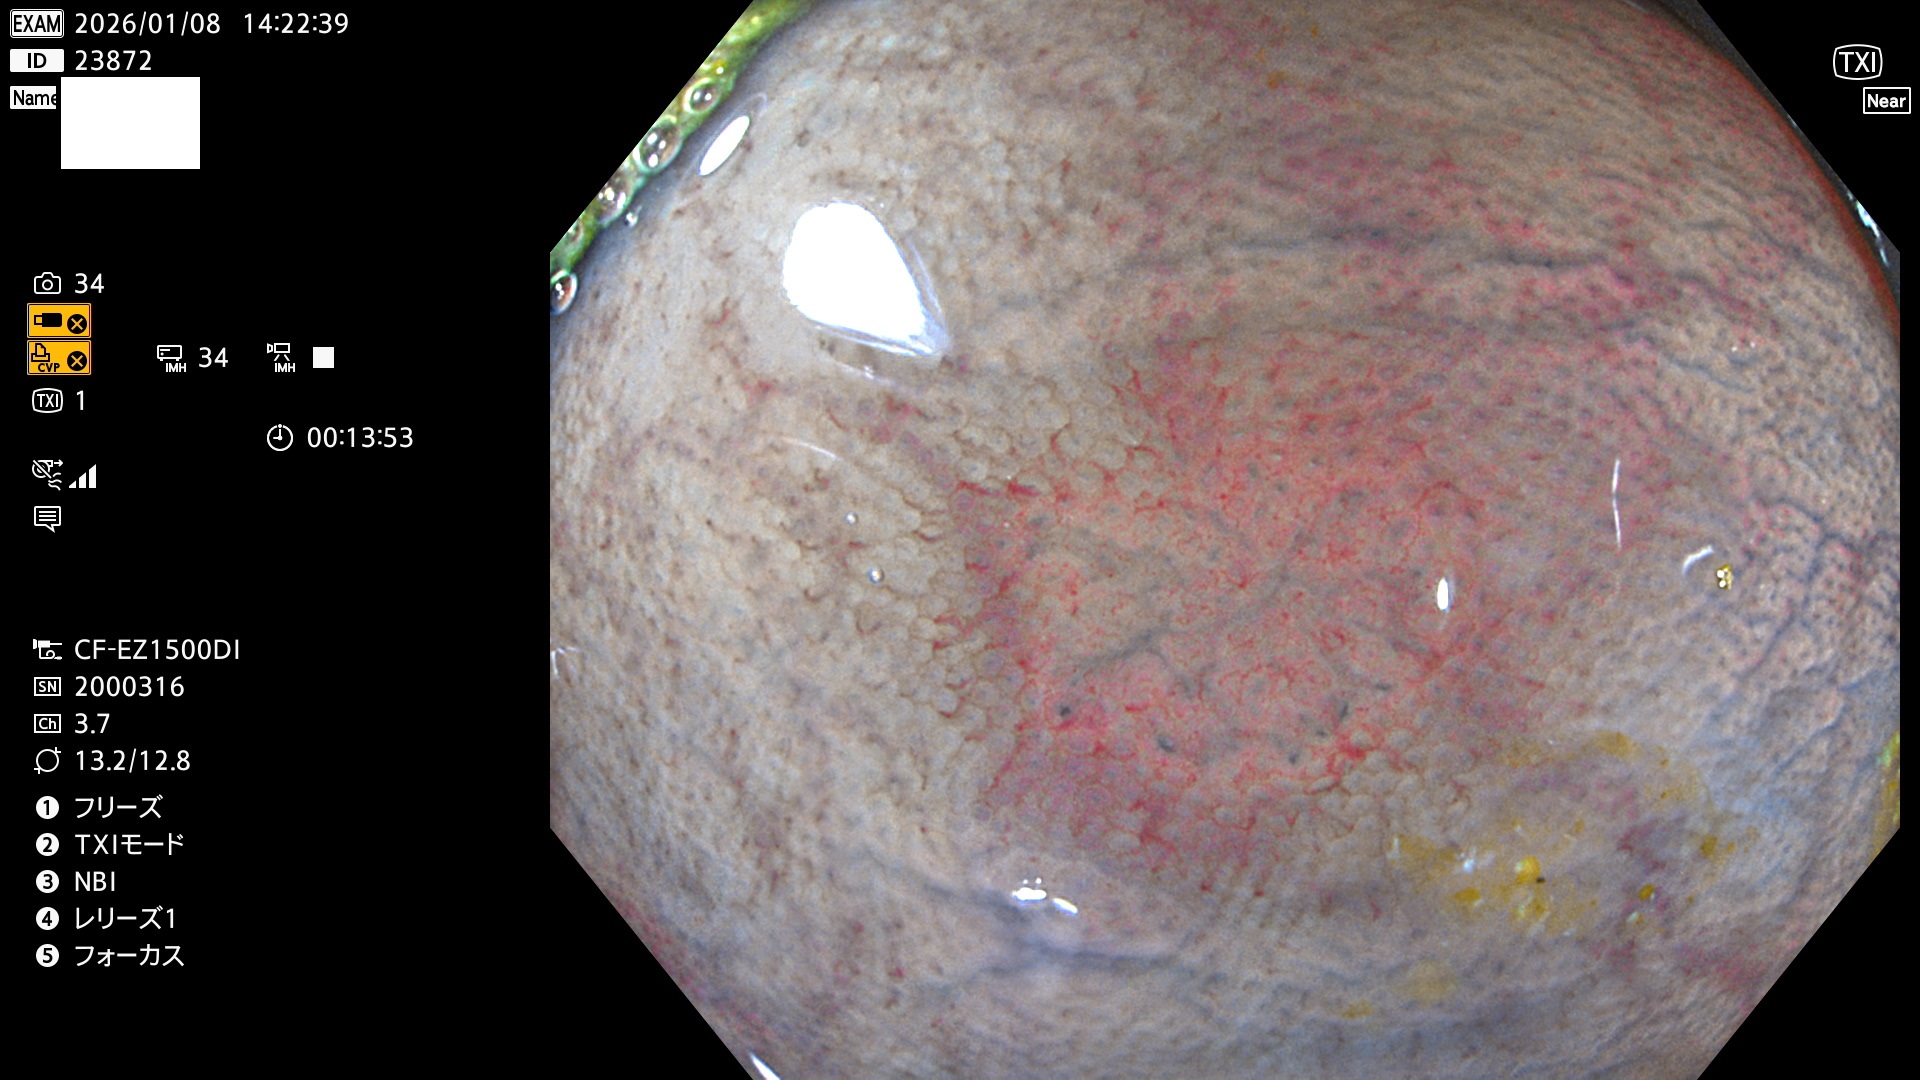

完全に平坦な物をUb、陥凹している物をUcと呼びます。Ubは認識が困難で、Ucはびらん(炎症)と紛らわしいために見落とされやすく、「内視鏡後・大腸癌」の原因になります。

専門的)Uc=De Novo癌? 内視鏡の解像度が低かった時代、このような説もありました。しかし今日の高精度内視鏡では良性の微小なUc型腺腫(APC遺伝子異常の腺腫)が日常的に見つかります。Ucこそが多段階発癌(Adenoma-Carcinoma Sequence)のMain Routeです。

毎週の検査(木・金・土・日)に発見されたUbとUc型・腺腫を、その週の日曜の夜にUPし1週間、提示します。

2026年1月8日〜1月11日の4日間(40件)6個 (Uc_ADR=6個/40人=15%)